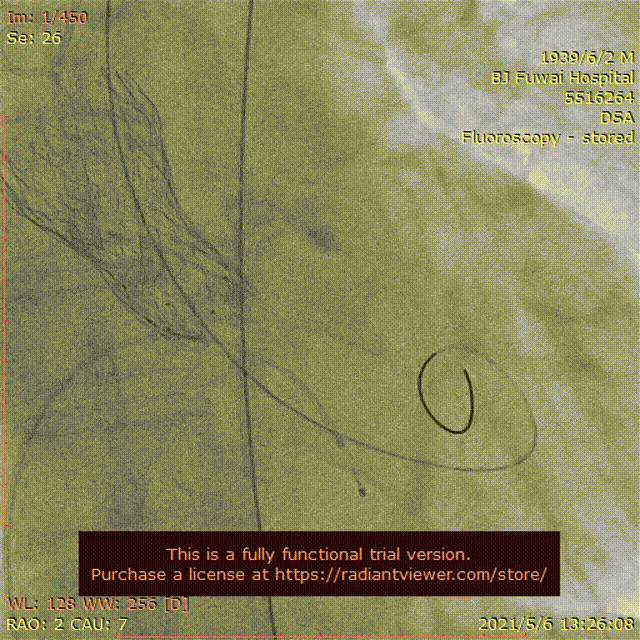

手术当天,病房护士提前行左肘正中静脉留置针作为补充液体通路;患者送达介入导管室后,省去经颈内静脉穿刺行中心静脉置管、经食道超声检查、术前导尿和麻醉师全身麻醉及气管插管或喉罩通气等过程;患者经过消毒及铺单后。半支(50mg)利多卡因局部麻醉后,穿刺右桡动脉作为辅入路,立即检测动脉血压;四支(400mg)利多卡因局部麻醉后,血管超声引导精准穿刺右股总动脉,两把ProGlide预埋处理后,作为主入路,置入20F 长导引鞘管(戈尔公司),立即动脉给予肝素5000单位;经右股静脉入路,将漂浮电极送入右心室心尖,临时起搏器调整至120次/分调试及测试患者的耐受性。主入路和静脉起搏器入路建立过程中,密切关注患者的血压心率等生命体征无明显异常,患者无明显不适。经右桡动脉送角度猪尾于右冠窦,采用右窦中心投照体位(右2°,足8°)行主动脉根部造影;

交换为头端塑形好的Landerquist超硬导丝,采用23 mm NUMED-II球囊对狭窄钙化的主动脉瓣进行预扩张,同时造影显示球囊完全封闭主动脉瓣,几乎无反流;

根据瓣上结构测量及球囊预扩张效果,采取“Down-size”策略,选择A-26 Venus A瓣膜,通过输送系统完成过弓和跨瓣;Venus A瓣膜精准定位于瓣环水平,

在临时起搏器控制心室快速起搏下完成瓣膜释放;

由于本例患者原瓣叶融合钙化较重,采用“瓣中瓣”技术植入另外一个A-26 Venus A瓣膜,

采用23mm NUMED-II球囊对植入的瓣膜进行后扩张;

最后造影显示新植入的瓣膜位置理想,少量瓣周反流,

跨瓣压差由术前30 mmHg下降至4 mmHg;即刻经胸超声评估主动脉瓣位植入生物瓣峰值流速为2.0 m/s,平均跨瓣压差为16 mmHg,少中量瓣周反流,左室射血分数为45%;评估患者心率为67次/分并且心电图较术前无明显异常,故即刻拔出临时起搏导线。整个手术过程仅采用局部麻醉,无任何镇静剂使用,患者全程清醒,配合良好,在球囊扩张主动脉瓣及瓣膜释放过程的血压及心率等生命体征与既往全麻相比无明显异常,患者略感心慌及无力。(图3)。术后患者平卧24 小时即下床活动,进行康复训练;采用阿司匹林100 mg (QD)和氯吡格雷75 mg(QD)行双联抗血小板治疗,术后4天顺利出院。

图3患者经导管主动脉瓣置换术及围术期操作

A:主动脉根部造影;B:23 mm球囊预扩张;C:26型号VenusA瓣膜植入;D:26型号VenusA“瓣中瓣”位置良好,少量瓣周漏;E和F:术前及术后经导管跨瓣压差;G:肘正中静脉留置针;H:患者全程清醒状态。